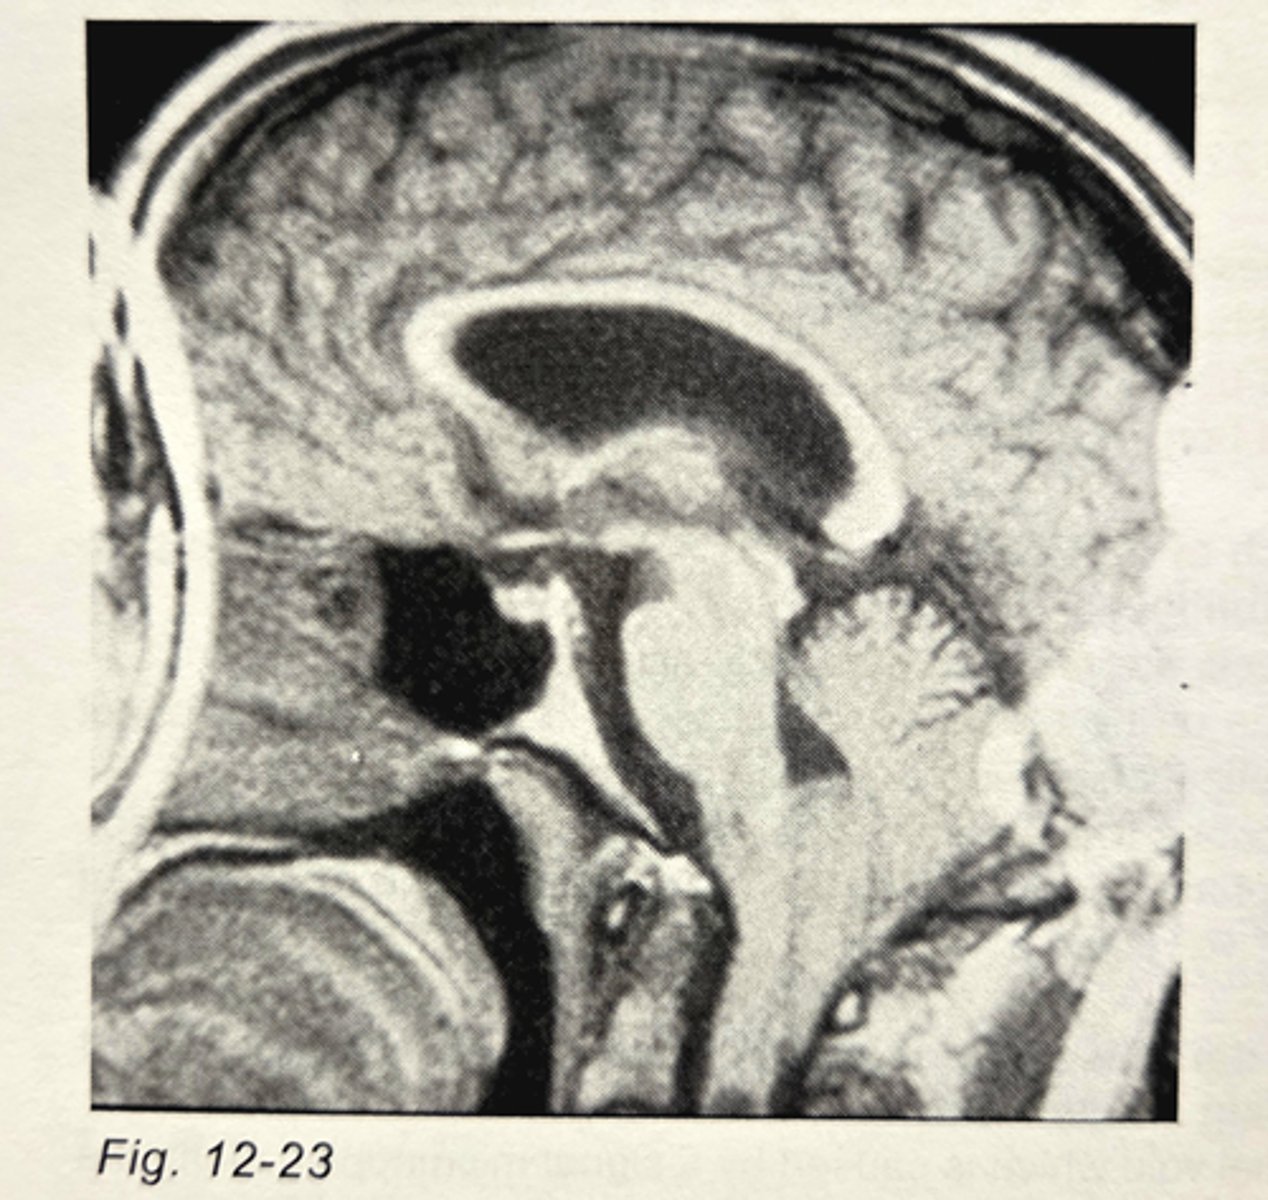

The image in Fig. 12-23 demonstrates an example of __________ artifact?

aliasing

If phase encoding was accomplished with the z-gradient, which of the following could eliminate the artifact from the image in Fig. 12-23 (assume the coordinate convention at the beginning of the post-test section)?

no frequency wrap option